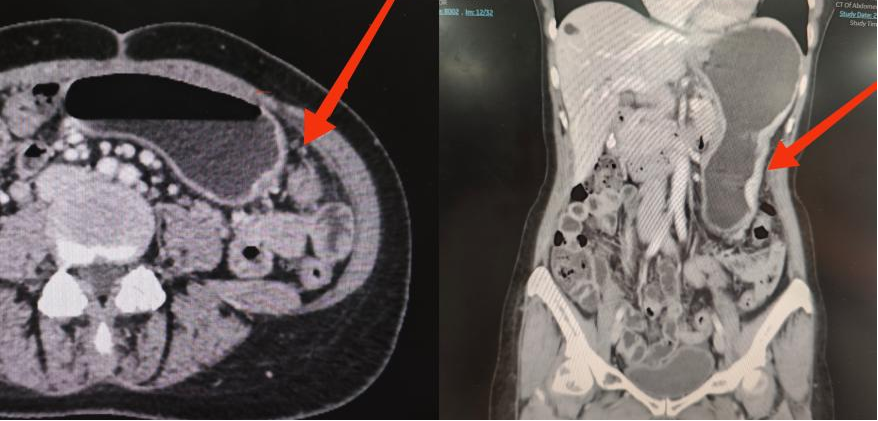

Aria术前影像报告,箭头处为转移病灶

可能是因为语言的障碍,也有可能是因为多次治疗后的无助,初次来到门诊的Aria看起来并没有什么信心。而李雁在诊疗过程中,以自己和团队的专业水平,逐步给了他们生的希望,顺畅的英语交流更是扫除了交流的最后一丝障碍。在术前进行MDT评估后,李雁团队制定了完善的手术方案:先通过细胞减灭术切除肉眼可见的肿瘤,再通过腹腔热灌注化疗消灭残余肿瘤组织和游离肿瘤细胞,力求彻底消灭腹腔内原发肿瘤和转移灶。